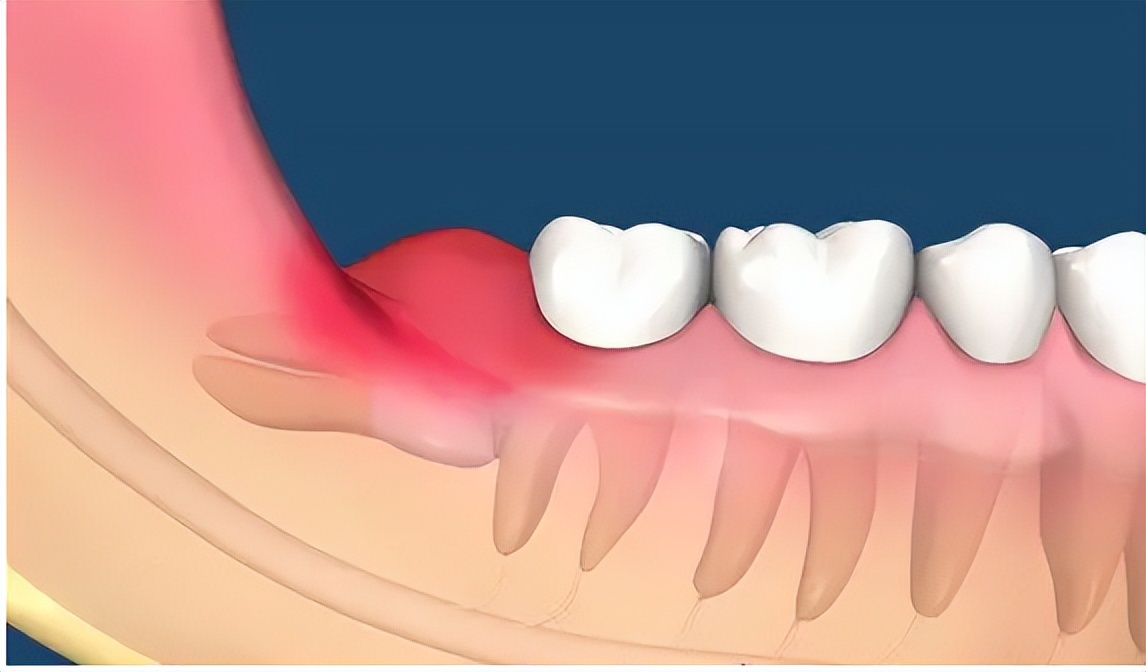

但由于智齿身处口腔最深处,临近喉咙,给日常清洁工作带来了很大难度,容易刷不干净,很容易发生蛀牙或发炎(智齿冠周炎),所以在日常保健中一定要做好口腔卫生。